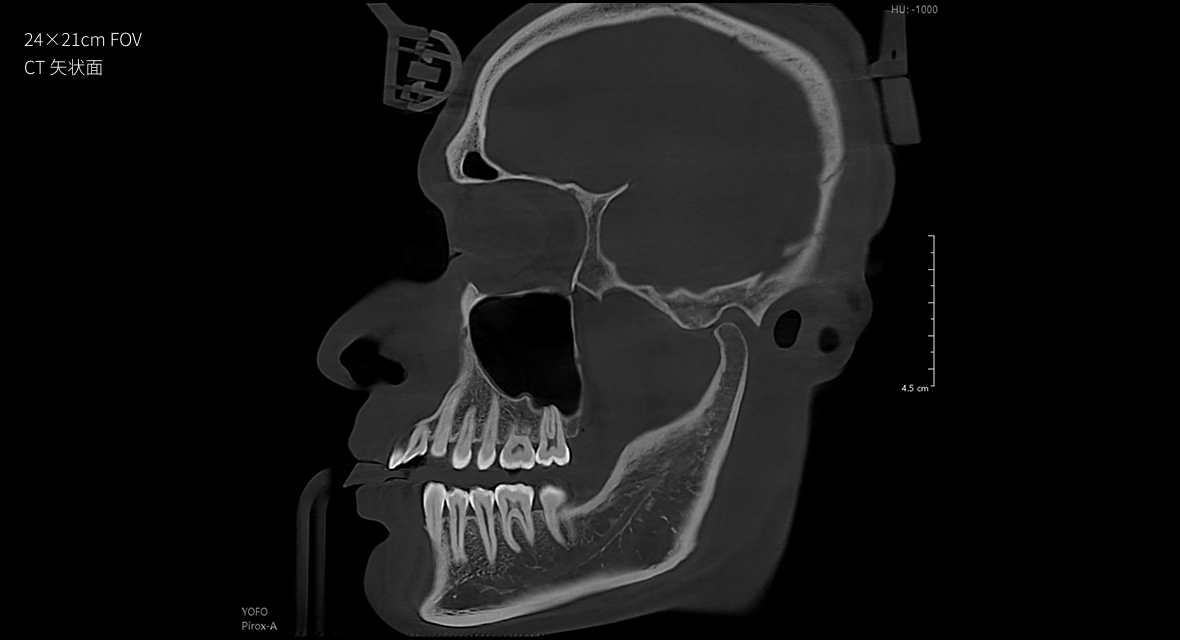

视野最大可至24×21cm

视野最大可至24×21cm,即使对于体型偏胖、脸型较大的患者,也都游刃有余。多种视野范围可供临床选择:24×21cm、16×13cm、5×5cm。

24×21的视野,可以完全覆盖患者上至额顶、下至颈角部位,前至鼻尖的范围